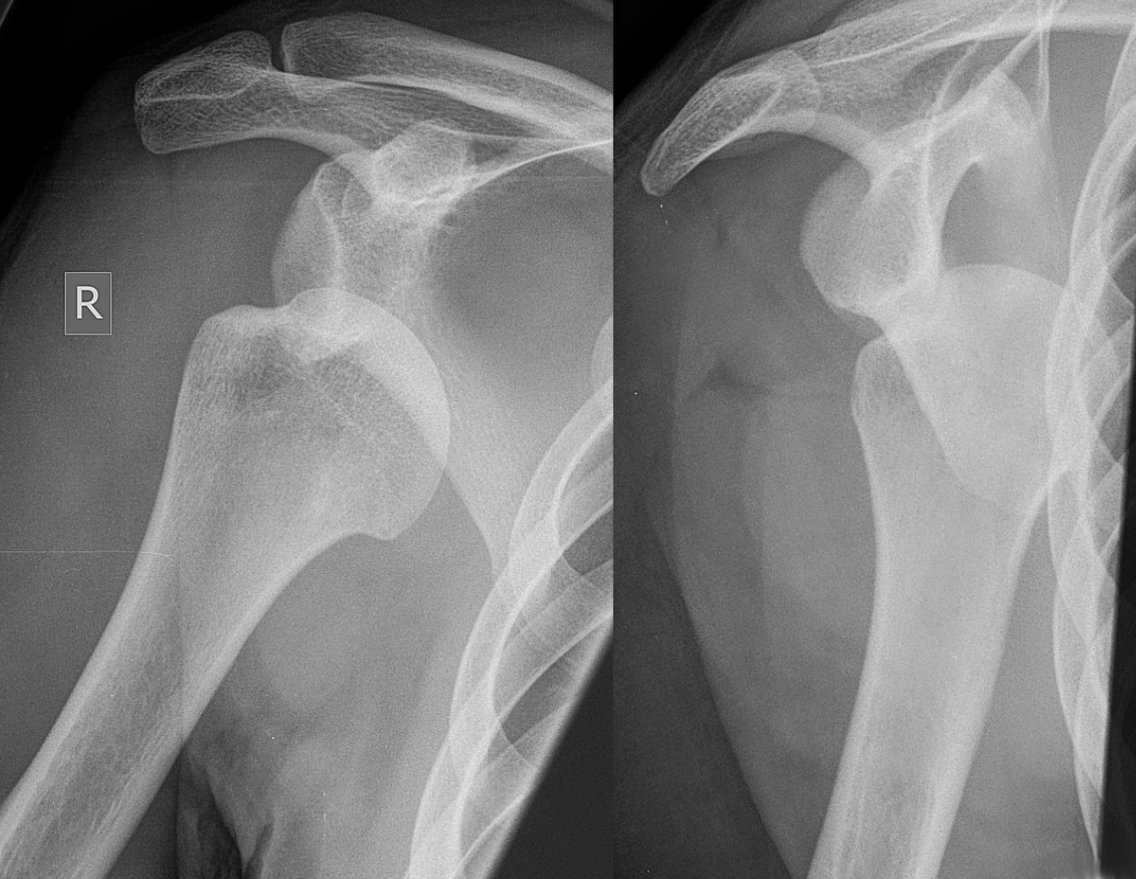

This worrisome (for some) shoulder XRAY actually has TWO associated injuries in one picture?

Anterior shoulder dislocation with Hill-Sach's deformity

Jordan G. with right shoulder pain?

Posterior shoulder dislocation

(electrocution and "convulsive" seizure MC mechanisms)